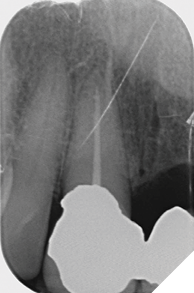

Radiographic examination shows the upper left lateral incisor tooth has decayed through and through and the upper right central incisor tooth is heavily root treated and filled (Figs. 1-2).

Fig. 1

Fig. 2